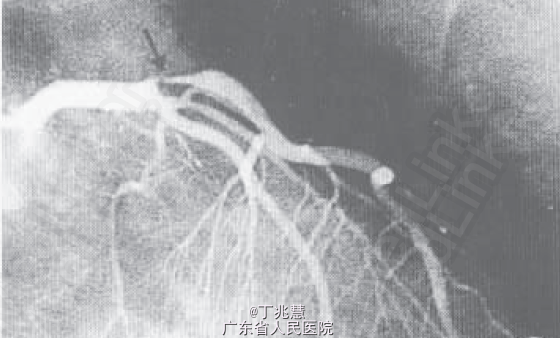

诊断:冠心病,陈旧下壁心肌梗死,劳累恶化型心绞痛; 处理:冠脉造影+支架植入术。